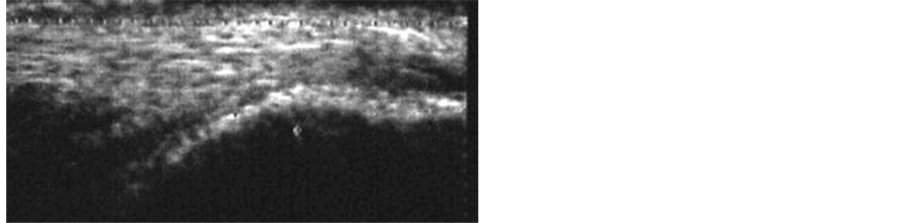

Color Power Doppler evaluation demonstrated a normalization of the microvascularity present before the beginning of the treatment in group A subjects (Figure 4).

No significant differences in the microvascularity of the group B subjects and no symptoms were observed (Figure 5). There were no significant side effects in either treatment groups, except for a temporary paratendon

edema in three subjects of the group A, which resolved by local cryotherapy in 48 hours without further consequences.

Figure 4. Group A, after 6 months: normal microvascularity and disappearance of the hypoechogenicity areas.

Figure 5. Group B, after 6 months: no change than before.